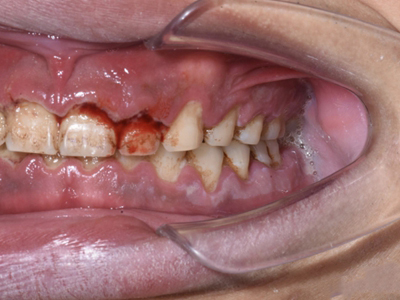

急性坏死性溃疡性龈炎起病急,病程短,常为数天至1-2周,以龈乳头和龈缘的坏死为其特征性损害,尤以下前牙多见,初起时龈乳头充血水肿,个别龈乳头顶端可发生坏死性溃疡,上覆有灰白色坏死物,中央凹下如火山口状。龈缘如虫蚀状,坏死区出现灰褐色假膜,擦去后可见出血创面。龈乳头被破坏后与龈缘成一直线,如刀切状。病损一般不波及附着龈,患处牙龈极易出血,疼痛明显并有腐败性口臭。

重症患者可有低热、疲乏等全身症状,并可伴有下颌下淋巴结肿大和压痛。有的患者可能进展为坏死性龈口炎、坏死性溃疡性牙周炎等疾病,从而导致牙周袋形成、牙槽骨吸收和牙齿松动。